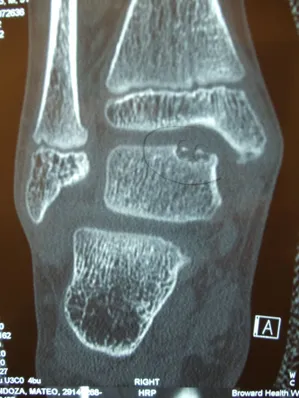

CT and MRI OCD Talus